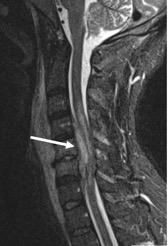

Patient med anamnes på missbruk inneliggande på infektionsavdelning på grund av feber, sjukdomskänsla och högt CRP. Han har också nackvärk och sedan i morse tilltagande svaghet i armar och ben. Magnetkamera visar uttalad prevertebral svullnad, spondylodiskit mellan C5 och C6, och epiduralabscess i halsryggen (pil).

Svar: Progredierande neurologi gör detta till ett mycket akut tillstånd. Patienten ska opereras så fort det är möjligt och oavsett tid på dygnet. Vanligaste tillvägagångssätt vid operation av spondylodiskit och epiduralabscess i halsryggen är främre dekompression och fusion men även bakre dekompression är möjlig.